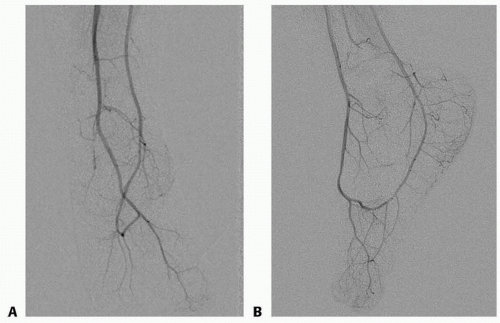

Routine angiography is debatable; nevertheless, it is the authors’ practice to obtain angiography of the hand and foot on most patients (FIG 4).

Angiography helps to create a road map and a plan for the operation. Questions such as the need for vein grafting (foot), end-to-side vs end-to-end anastomoses (hand), and residual vascularity of the foot after flap harvest can be answered preoperatively. This planning is essential in cases where a team approach with multiple surgeons is undertaken. Certainly for patients with abnormal foot anatomy (FIG 5), angiography helps with preoperative planning to ensure a viable flap.